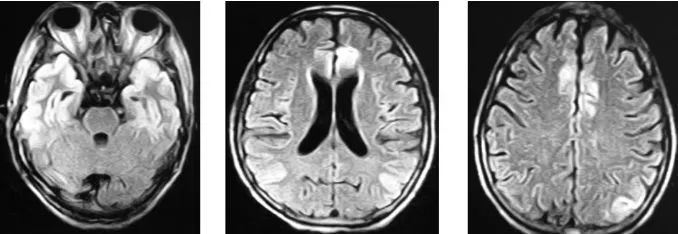

头颅MRI:双侧额颞枕叶可见长T2。

FLAIR呈高信号异常。